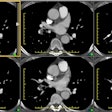

PURPOSE: To evaluate the feasibility and safety of endovascular stent-graft

placement in treating Stanford type B aortic dissection. MATERIALS AND METHODS:

Seven patients underwent endovascular stent-graft placement for type B aortic

dissection. Five patients had acute and two had chronic dissection. In five

patients, the proximal entry tear was within 2 cm of the origin of the left

subclavian artery, and in two patients it was beyond this site. In three

patients, the noncovered proximal portion of the stent-graft was placed across

the origin of the left subclavian artery. The efficacy of the procedure was

assessed at follow-up studies 3, 6, 12, and 24 months after intervention.

RESULTS: The procedure was technically and clinically successful in six patients

(86%). The left subclavian artery remained patent in all patients. In two

patients with involvement of aortic branches, endovascular stent-graft placement

restored adequate blood flow to the compromised branches. One patient was

readmitted 1 month later because the dissection extended into the ascending

aorta. In all but this patient, closure of the entry tear and thrombosis of the

false lumen along the stent-graft were achieved. All false lumina shrank

considerably. The mean follow-up time was 14 months (range, 1-25 months).